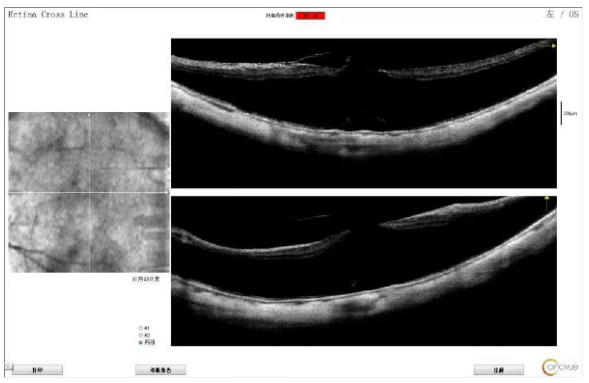

1 简要病历

患者,女性,63岁,因左眼缓慢视力下降伴视物变形1年就诊。重要专科检查:最佳矫正视力(best corrected visual acutiy,BCVA)为?13.00DS/?2.50 DC=0.2,晶状体浑浊分级(lens opacities classification system III,LOCS III)为C1N3P1,眼底豹纹状,黄斑区色素紊乱。光学相干断层扫描(optical coherence tomography,OCT) 示左眼黄斑劈裂、黄斑裂孔伴前膜(图1)。非手术眼(右眼)BCVA-11.00DS/-2.00DC=0.3,晶状体浑浊分级C1N2P1,眼底豹纹状,黄斑区色素紊乱。

图1 术前OCT示左眼黄斑劈裂、黄斑裂孔伴黄斑前膜

Figure 1 The OCT measurement indicated macular retinoschisis and macular hole complicated with epiretinal membrane for the patient's left eye